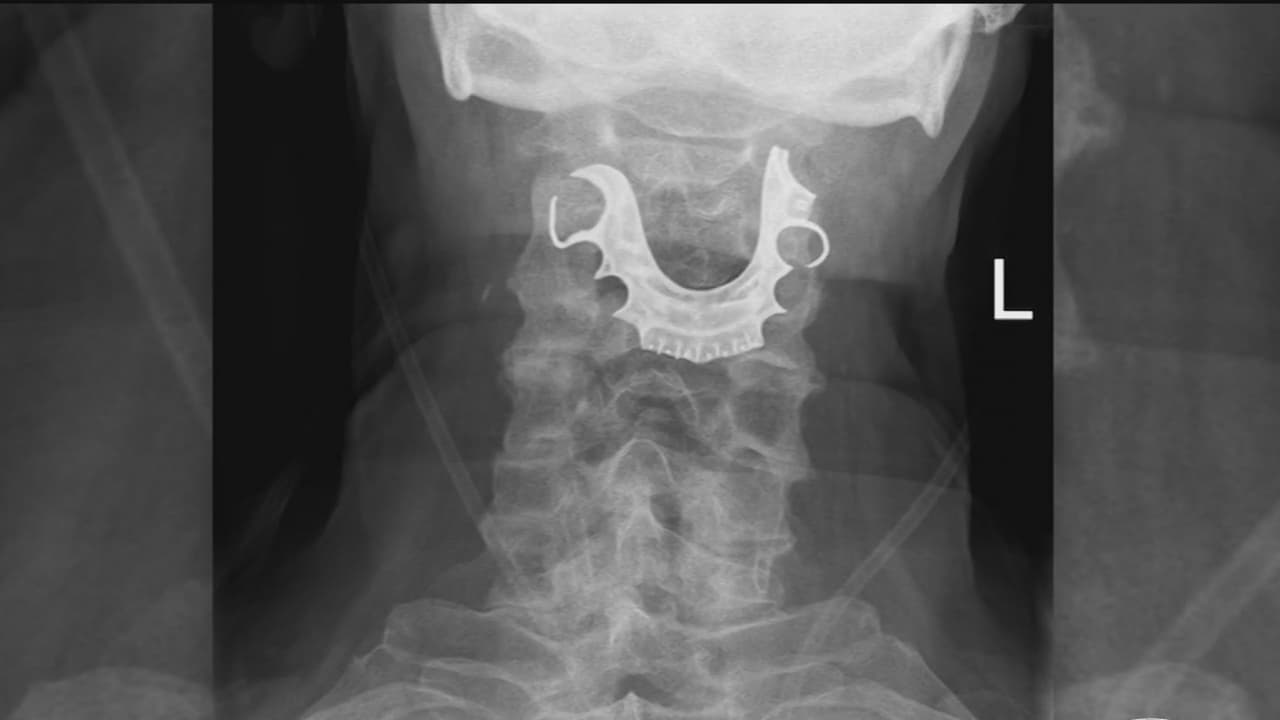

El paciente volvió al centro médico en Reino Unido por dificultades para respirar después de la intervención quirúrgica. Los estudios que le realizaron arrojaron que mientras estaba en el salón de operaciones se había tragado varias piezas de su dentadura postiza, por lo que tuvo que ser operado nuevamente.